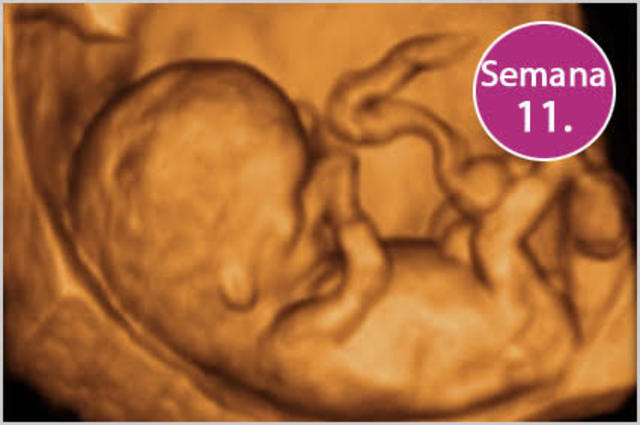

• Semana 11

Semana 11

el bebé empieza a generar sus propios glóbulos rojos. Además, comenzará a producir orina, el principal componente del líquido amniótico. La piel es todavía transparente y su cuerpo se va alargando. Aun así, la cabeza es un tercio del largo del cuerpo.

el embrión ha aumentado 5 veces de tamaño, 200 células han tomado posiciones y algunos músculos y nervios se mueven. Tiene hígado, riñones y un estómago del tamaño de un granito de arroz.